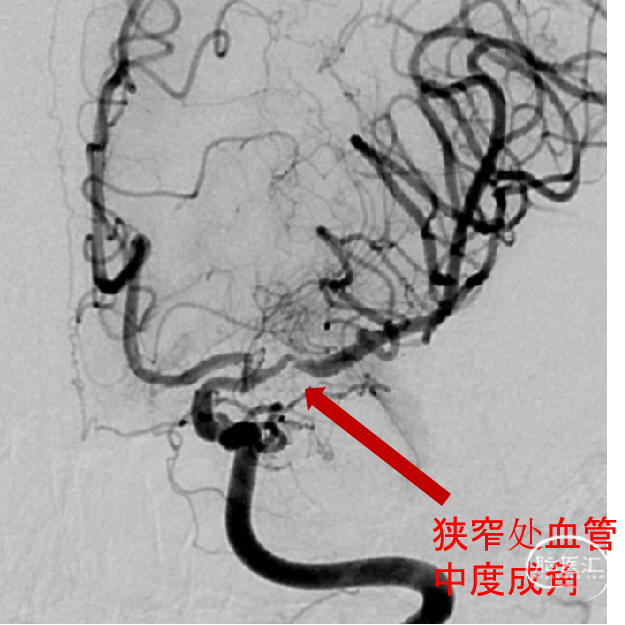

发病一周后完善了脑血管造影检查 。

正位

侧位

左侧大脑中动脉前向血流较同侧大脑前动脉缓慢。

3D:左侧颈内动脉C7段中度狭窄,左侧大脑中动脉M1段重度狭窄。

考虑狭窄处血管成角,拟置入经导管释放自膨式开环支架Neuroform® EZ